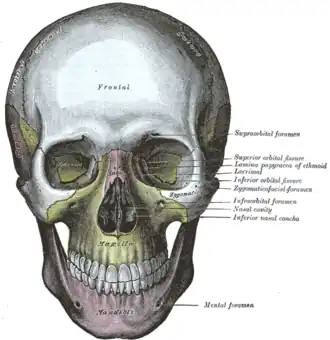

Articulation de l'os palatin gauche avec le maxillaire. Le crâne de face.